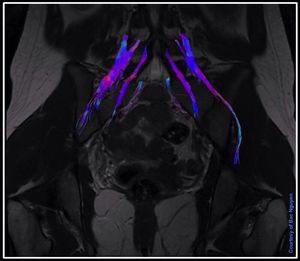

MR Neurography of lumbosacral plexus. RS-EPI (RESOLVE) DTI with 20 directions. Siemens Prisma 3 Tesla. Image courtesy of Bac Nguyen. #MRI #DTI